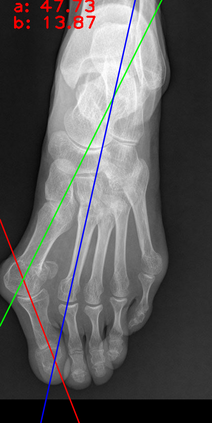

Angular measurements is essential to make a resonable treatment for Hallux valgus (HV), a common forefoot deformity. However, it still depends on manual labeling and measurement, which is time-consuming and sometimes unreliable. Automating this process is a thing of concern. However, it lack of dataset and the keypoints based method which made a great success in pose estimation is not suitable for this field.To solve the problems, we made a dataset and developed an algorithm based on deep learning and linear regression. It shows great fitting ability to the ground truth.